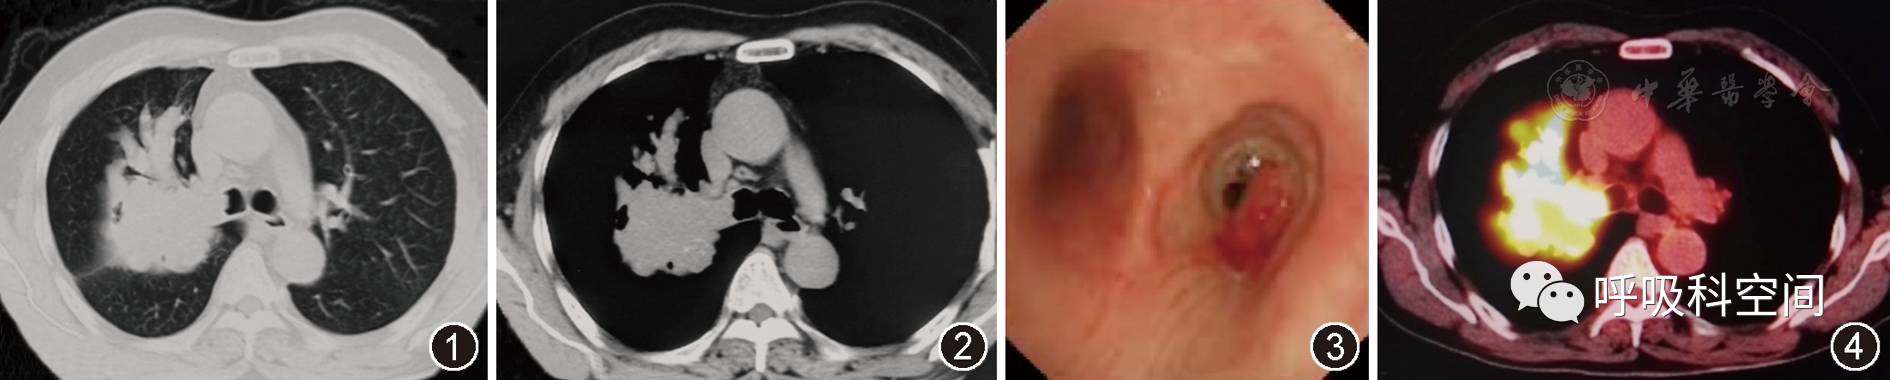

患者男,60岁。主因"间断咳嗽、喘息1年,伴痰中带血1个月"于2015年12月20日入院。患者1年前无明显诱因出现咳嗽,咳少量白痰,伴喘息,未予重视。后喘息间断发作,可自闻及喘鸣音,活动后明显。近1个月来出现痰中带血,伴纳差、乏力,体重下降。行胸部CT示右肺上叶团块状高密度影,边缘不规整,局部呈"指套征"(图1,图2)。既往吸烟指数800年支,未戒烟。体检:浅表淋巴结未触及肿大,右上肺呼吸音减低,未闻及干、湿性啰音。心腹未见异常。入院初步诊断:肺部阴影原因待查,肺癌?变应性支气管肺曲霉病?

2015年12月15日胸部CT平扫肺窗(图1) 示右肺上叶团块状高密度影,边缘不规整,病变沿支气管分布,右上叶前段支气管扩张,呈"指套征"。右肺上叶支气管闭塞,右主支气管管腔内可见结节样突起。纵隔窗(图2) 示肿块内局部可见多发点状钙化影,"指套"近端呈软组织密度影(47 HU),远端为黏液嵌塞密度影(25 HU)

图3

支气管镜示右主支气管外侧壁可见息肉样新生物生长,表面血运丰富,致右上叶支气管开口闭塞、右主支气管管腔明显狭窄

图4

PET/CT示右肺上叶肿块影,放射性摄取明显增高,最大SUV值约13.5,考虑恶性病变

住院后查血常规正常,嗜酸粒细胞计数正常。血清总免疫球蛋白E(IgE)和曲霉特异性免疫球蛋白E均正常。血癌胚抗原84.56 μg/L(正常参考值:0~5 μg/L)、鳞状细胞癌抗原1.8 μg/L(正常参考值:<1.5 μg/L)。痰找结核菌和真菌结果均阴性。1,3–β–D–葡聚糖和曲霉半乳甘露聚糖抗原均正常。支气管镜示右主支气管外侧壁可见息肉样新生物生长(图3)。给予右主支气管新生物行活检,病理示肺鳞癌。全身PET–CT显示右肺上叶不规则肿块影,代谢异常活跃,考虑恶性,伴右侧肺内多发转移,右侧肺门、纵隔多发淋巴结以及胰腺转移(图4)。最终诊断:肺鳞癌,Ⅳ期,T3N2M1。